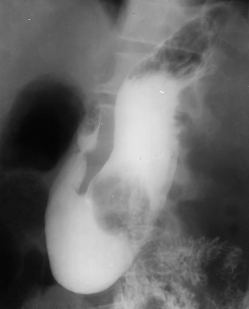

Hernie hiatală

Hernie hiatală prin alunecare

Hernie hiatală prin rostogolire

Hernie hiatală - brahiesofag